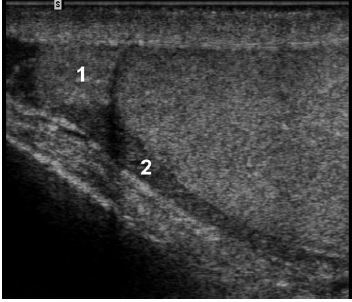

A

Transverse and longitudinal views of

the mediastinum of the testis